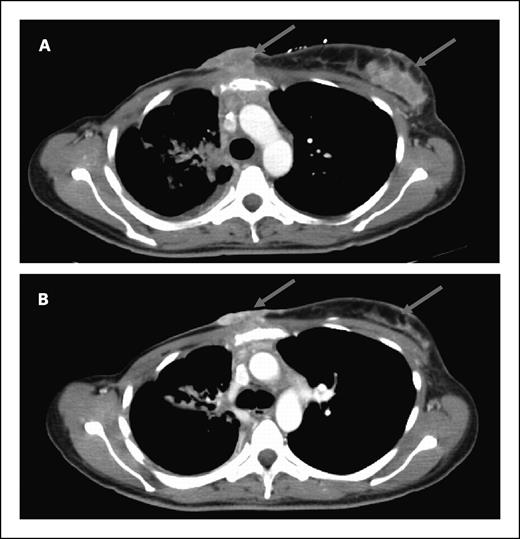

Antitumor activity. Of the 22 accessible patients, none had a complete or partial response by response evaluation criteria in solid tumors. Eleven patients had stable disease as the best response. The median duration of stable disease was 3 months (range, 1.5-8 months). One patient with Her2-negative breast cancer had a 29% reduction in target lesions after two cycles (Fig. 1). Minor responses in target lesions were seen in four other patients: non–small cell lung (−13%), head and neck squamous cell (−10%), colorectal (−9%), and pancreatic adenocarcinoma (−8%). One patient with ampullary adenocarcinoma had improvement of carcinomatosis and a decrease in CA19-9 from 1,346 to 174 units/mL. All patients who showed tumor measurement reductions were irinotecan-naïve. One patient with irinotecan-refractory colorectal cancer was treated on the current study for five months. Tumor p53 status was available for 16 patients. Two of six patients with wild-type p53 had stable disease compared with 5 of 10 patients with mutant p53 (P = 0.63; Fisher's exact test).

Computed tomography of a patient with Her2-negative p53-mutant metastatic breast cancer before (A) and after two cycles (B) of 17AAG and irinotecan given at the MTD, showing regression of chest wall metastases (arrows).

Computed tomography of a patient with Her2-negative p53-mutant metastatic breast cancer before (A) and after two cycles (B) of 17AAG and irinotecan given at the MTD, showing regression of chest wall metastases (arrows).

No complete or partial responses were noted in this study. However, one patient with breast cancer showed a 29% reduction in index lesions, and five other patients showed tumor shrinkage. Although it may be difficult to separate the activity of the combination from that of irinotecan alone, as all patients who showed tumor shrinkage were irinotecan-naïve, we were encouraged to see signs of antitumor activity in this heavily pretreated group. Preclinical studies have suggested that tumors with intrinsic checkpoint defects, by virtue of p53 loss, may be more susceptible to undergoing G2-M checkpoint abrogation and apoptosis induced by treatment with 17AAG and irinotecan. In our trial, two of six patients with wild-type p53 had stable disease compared with 5 of 10 patients with mutant p53. The relationship between tumor p53 status and response to this drug combination therefore deserves further exploration. Given the encouraging response data seen in a recently completed phase II study of 17AAG and trastuzumab in trastuzumab-refractory Her2-positive breast cancer (21) and the 29% tumor shrinkage observed in a patient with Her2-negative disease in the current study, breast cancer would potentially be a tumor type in which the combination of irinotecan and 17AAG could be further developed.

Of note, the patient with the pharmacodynamic responses shown in Fig. 3 was taken off the study for “early disease progression” after experiencing increased fatigue and abdominal pain during cycle 1. An imaging study done after only one combination treatment of irinotecan and 17AAG revealed tumor progression in the liver. However, retrospective examination of the computer tomography done for tumor biopsy after irinotecan alone showed already substantial tumor progression when compared with baseline. It is possible that the pharmacodynamic effects observed in this patient preceded subsequent radiologic response if this patient was allowed to continue on study.